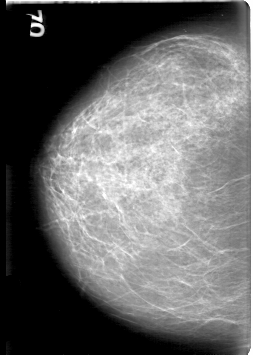

D_4086_1.LEFT_MLO

LEFT_MLO LINES 5296 PIXELS_PER_LINE 4051 BITS_PER_PIXEL 12 RESOLUTION 43.5 OVERLAY